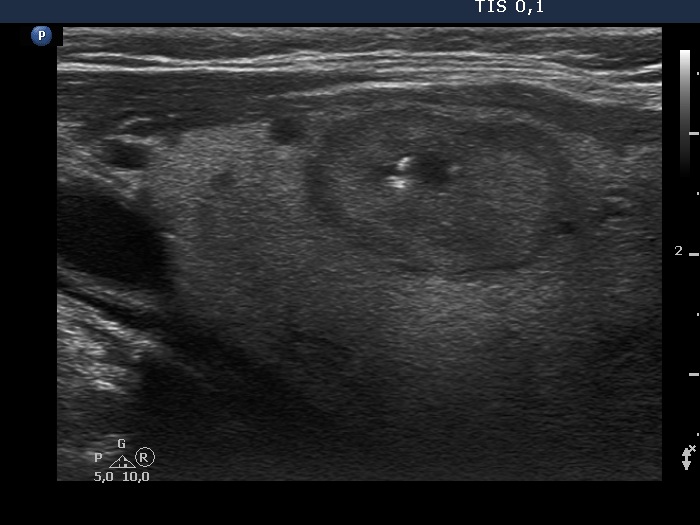

Ultrasonography. The thyroid was echonormal and contained several nodules of different echogenicities including a hypoechogenic one in the dorsal part of the left lobe and a minimally hypoechogenic lesion presenting groups of echogenic foci in the ventral part of the left lobe.

The origin of the echogenic foci within the left nodule is equivocal. They probably correspond to groups of smaller echogenic foci.